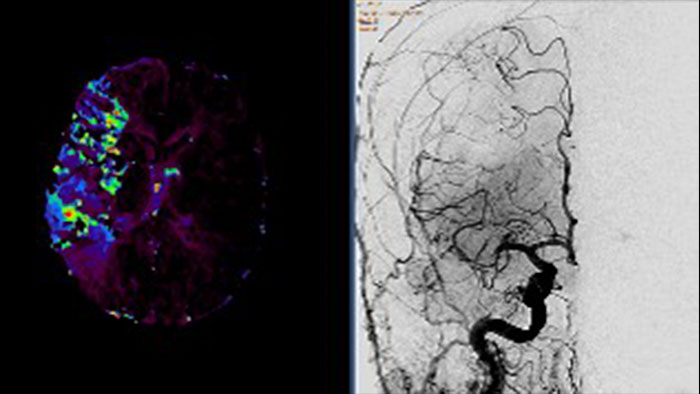

- Dynamic Myocardial Perfusion (DMP)

CT Dynamic Myocardial Perfusion (DMP)

Dynamic color maps provide an assessment of myocardial risk

Provides automatic and manual tools to help visualize and assess signal intensity differences (in Hounsfield Unit) focusing on the left ventricular myocardium, providing quantitative myocardial perfusion measurements for CT images.

Benefits

- Supports axial, ECG-gated CTA images, consisting of multiple time shots within the same acquisition of the myocardial region over time (i.e. dynamic CT scans), after an injection of intravenous contrast.

- Automatic and manual tools providing quantitative myocardial perfusion parameters such as: Peak Enhancement, Time To Peak, Perfusion and Blood Volume, and provides color maps representation of the results and graphical representation of intensity curves.